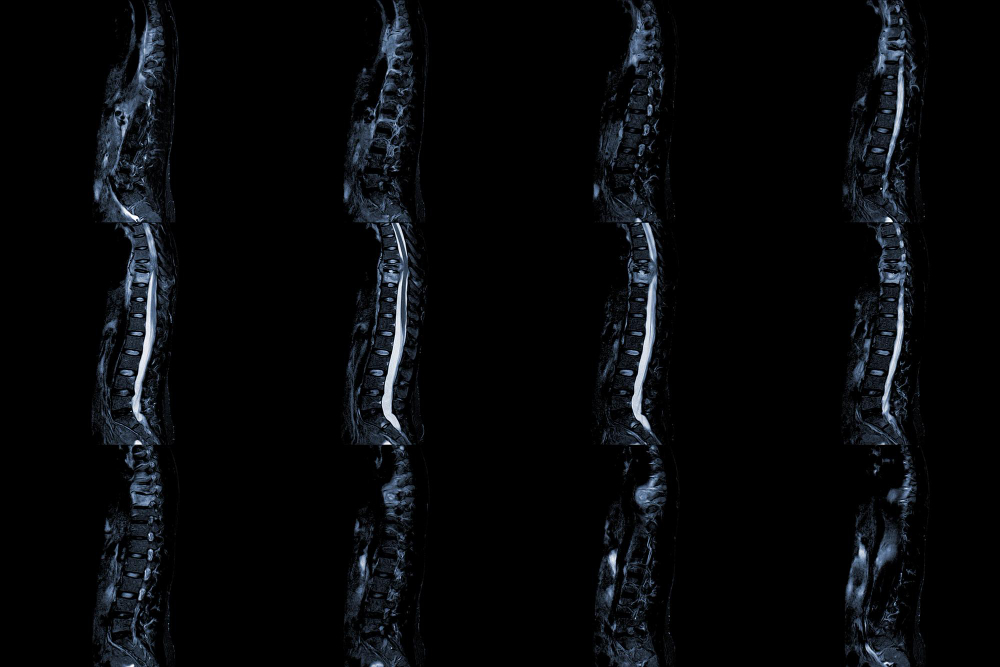

Disc replacement is a surgical procedure to treat chronic back pain caused by damaged or degenerated intervertebral discs. It involves removing the affected disc and replacing it with an artificial disc implant to restore disc height and mobility.

During surgery, our experts make an incision in the abdomen or neck, depending on the affected disc's location. The damaged disc is removed, and an artificial disc made of metal, plastic, or a combination of materials is inserted. The artificial disc mimics natural movement and function for improved mobility and pain relief.